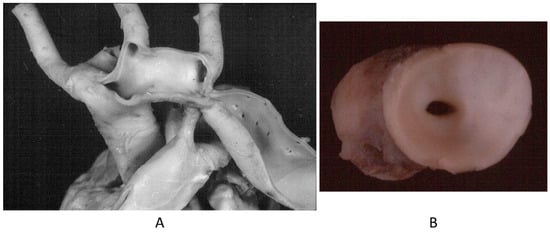

A rare CHD, reaching even the elderly, is corrected transposition of the great arteries (Figure 4A). The term “corrected” means “physiologically corrected” by atrioventricular and ventriculoarterial discordance in sequence, ensuring normal physiology of the blood stream (systemic and pulmonary circulations in series and not parallel, as in complete transposition) [16]. In this CHD, the AV conduction is located anteriorly with progressive fibrotic degeneration of the His bundle, putting the patient at risk of sudden death by AV block [17] (Figure 4B). Oddly enough, complete transposition may also exceptionally reach adulthood when associated with pulmonary stenosis and a ventricular septal defect.

Figure 4.

(A) Corrected transposition with atrioventricular and ventricular arterial discordance. (B) The AV node is anteriorly located and the His bundle interrupted by fibrosis. From a 43-year-old female with sudden death by AV block. A = aorta; LA = morphologically left atrium; LV = morphologically left ventricle; P = pulmonary artery; RV = morphologically right ventricle, RA= morphologically right atrium.